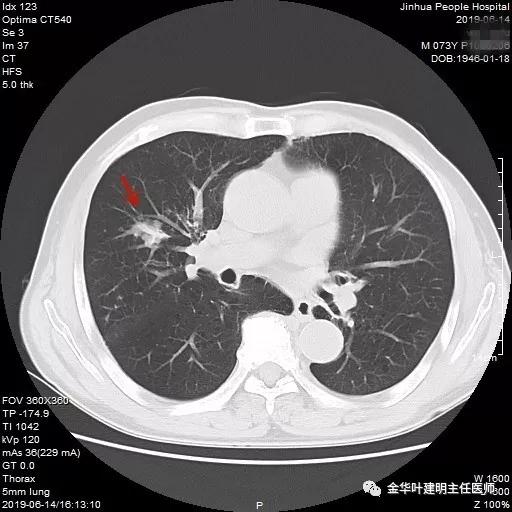

近日,同事再联系了我,说他同村的吴某已经决定来院接受手术治疗。所以就再次收住入院,予以复查了胸部CT增强,结果如下:

病灶较前有进展,更加膨隆了,直径也有所增加,好在仍未见明显纵隔淋巴结转移(特别肿大的淋巴结,但没有查PET评估)。其肺功能评估情况如下: